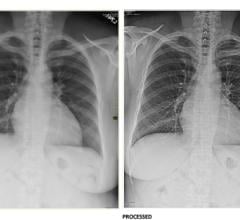

In a recent study and white paper, Frost & Sullivan concluded that Agfa HealthCare’s DR platform, highlighted by its MUSICA image processing software, is “well differentiated” from the competition and meets “best of breed” status by addressing “The Three Pillars of Digital Radiography’s Value Proposition:” producing excellent image quality, keeping radiation dose as low as reasonably achievable and enabling high workflow productivity.

Ashley County Medical Center, Crossett, Ark., is the first hospital in the United States to install Carestream’s DRX-Excel Plus radiography/fluoroscopy (R/F) system.